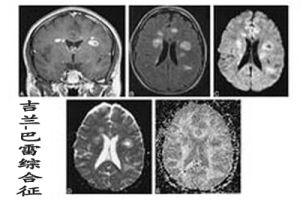

1.Fisher綜合徵:Fisher綜合徵是Fisher於1956年首先報告。有5大特點:

①雙側眼外肌麻痹;

②雙側對稱性小腦共濟失調;

③深反射消失;

④腦脊液蛋白細胞分離;

⑤預後良好